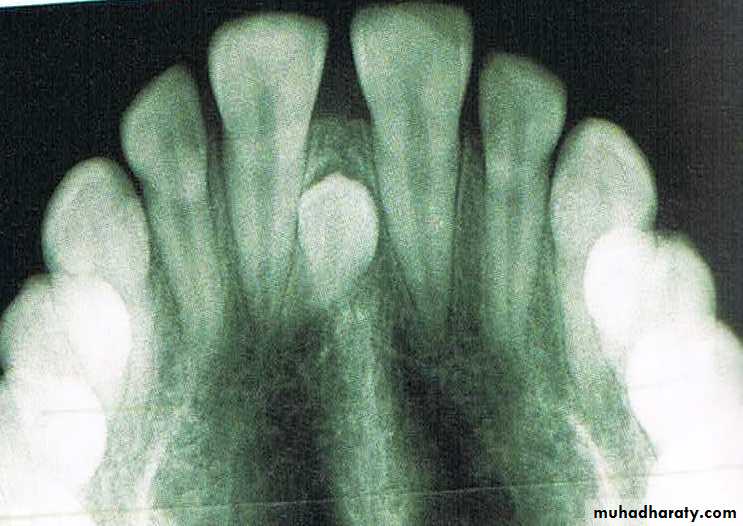

b) Mesiodens

Presence of an unerupted mesiodens between the two central incisors also predispose to midline diastema.56

• e. periapical radiograph:- presence of notching in the interdental bone is a diagnostic of a thick and fleshy frenum.

• f. midline radiographs will help in diagnosing midline pathology.